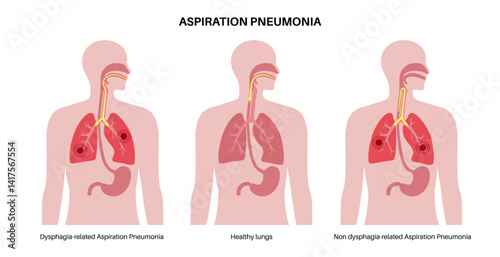

Aspiration - Posters, Wall Art, Canvas Prints